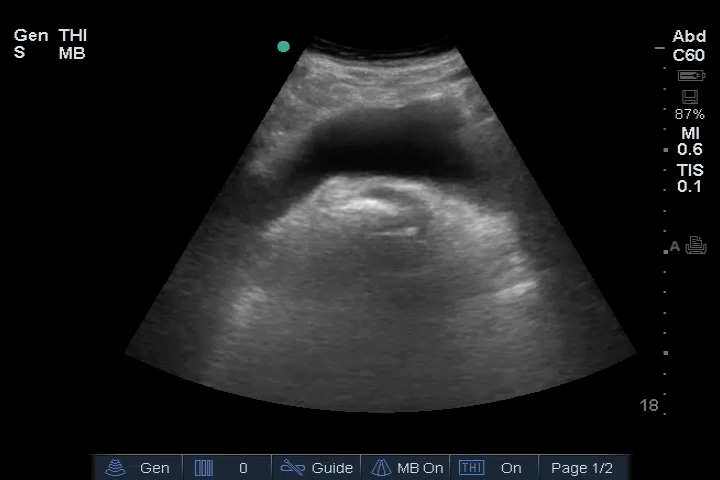

12_Heart_PLAX – Dilated RV, RA embolus

Heart: Dilated right ventricle (RV), most clearly visualized in the PSAX view. An embolus is visible in the right atrium (RA).